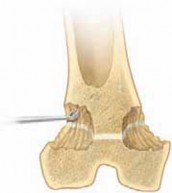

2. To avoid injury to the common peroneal nerve with a percutaneous epiphysiodesis of the proximal fibula, direct the curette into the anterosuperior area of the proximal epiphysis and then inferiorly into the physis of the proximal fibula (

TECH FIG 3A

).

1. The most superior extent of the fibular epiphysis proximally is usually at the level of the tibial physis.

3. The curette is used to ablate the entire central area of the physis of the fibula to achieve the epiphysiodesis (

TECH FIG 3B

4. The surgeon should not exit the cortex of the fibula as the central area is ablated.

B

--- ATECH FIG 3 • A. Dissection of the common peroneal nerve at the level of the fibula head. The nerve passes posteriorly and inferiorly to the fibula epiphysis.B. Technique of percutaneous epiphysiodesis of the fibula proximally. To avoid injury of the common peroneal nerve, the curette is directed into the anterosuperior area of the proximal epiphysis and then inferiorly into the physis of the fibula. (The most superior extent of the fibular epiphysis proximally is usually at the level of the tibial physis.) The curette is used to ablate the entire central area of the physis of the fibula to achieve the epiphysiodesis. The surgeon should not exit the cortex of the fibula as the central area is ablated. Discrepancy between bone age ■ In such cases, I prefer to use the bone age. Another choice is to use a stapling technique and chronological age (or figure 8 plate-screw), which preserves the physis, rather than epiphysiodesis.